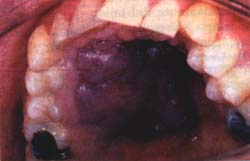

La lesión se ubica de preferencia en el paladar, en la encía y en la lengua 7 , y su tamaño puede alcanzar desde unos pocos milímetros hasta varios centímetros. Como en el SK cutáneo la presentación clínica varía desde una lesión inicial plana de color rojo o violáceo hasta una lesión de aspecto nodular, con o sin la presencia de ulceración (Figras 1-3); su presencia en forma intraósea en los maxilares es rara 8.

Figura 2. Etapa avanzada de un Sarcoma de Kaposi que ocupa casi todo el paladar duro.